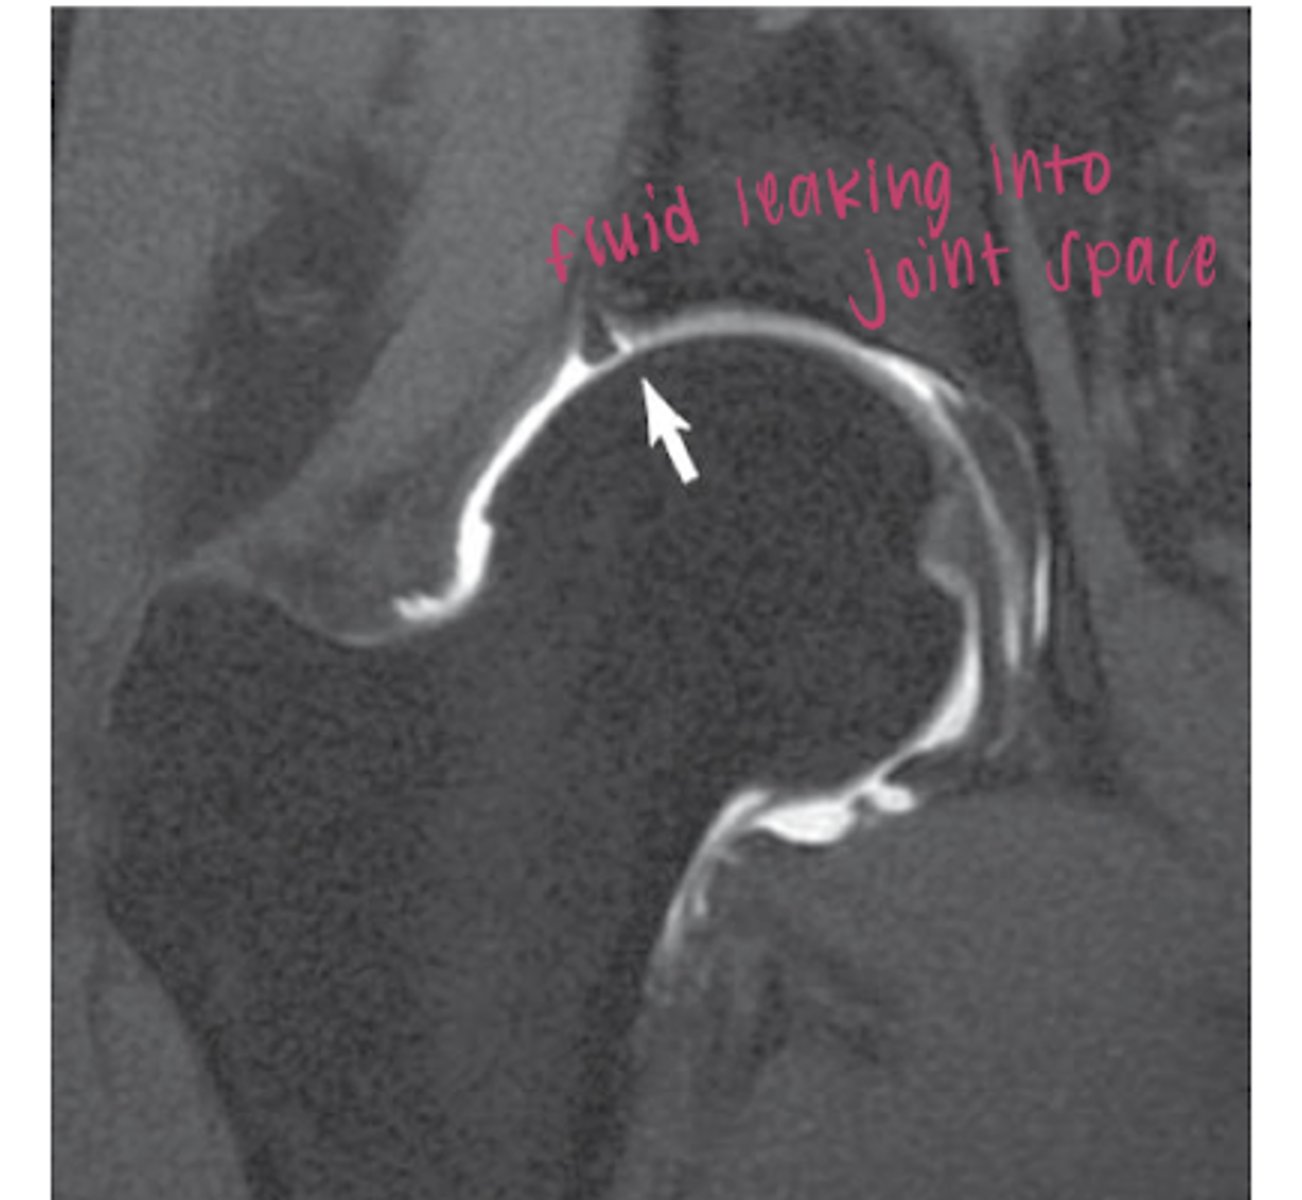

MR arthrogram of labral tear